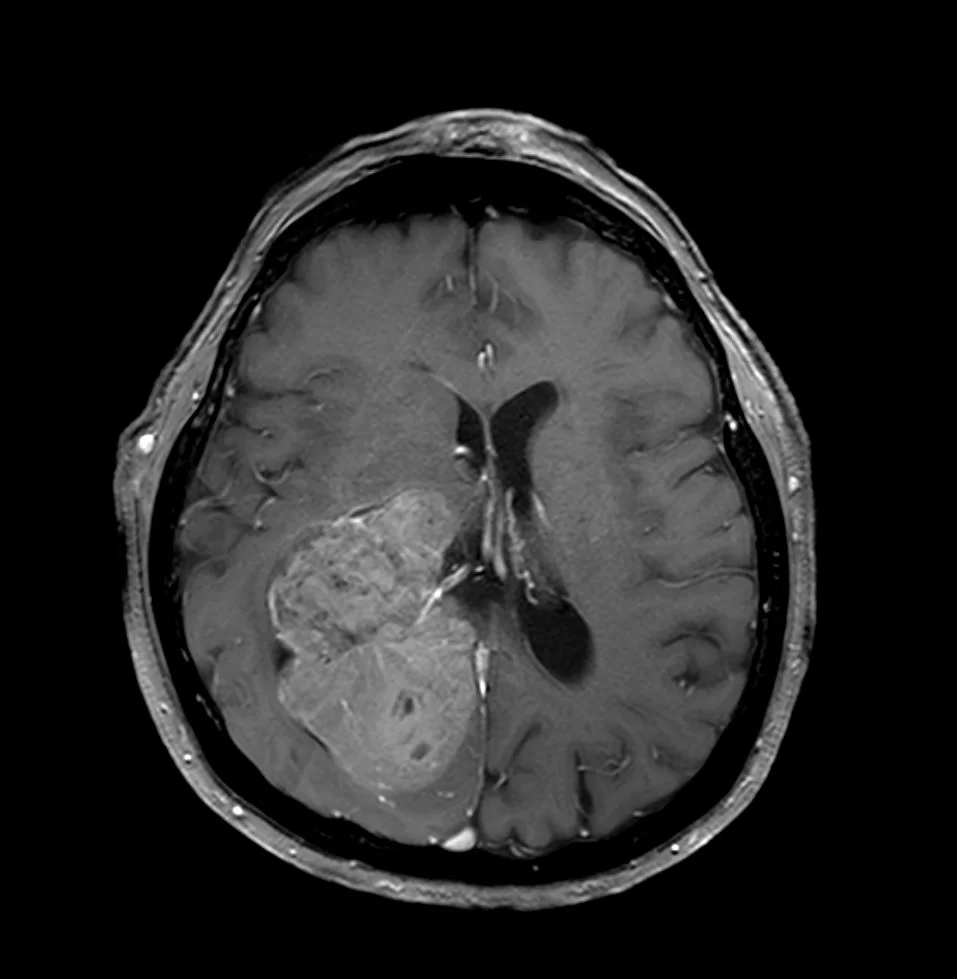

Ασθενής άνδρας, 31 ετών με επεισόδια κεφαλαλγίας. H Μαγνητική Τομογραφία εγκεφάλου ανέδειξε εκτεταμένη χωροκατακτητική εξεργασία δεξιά κροταφικά με πίεση επί του σύστοιχου κροταφικού κέρατος και

Περισσότερα